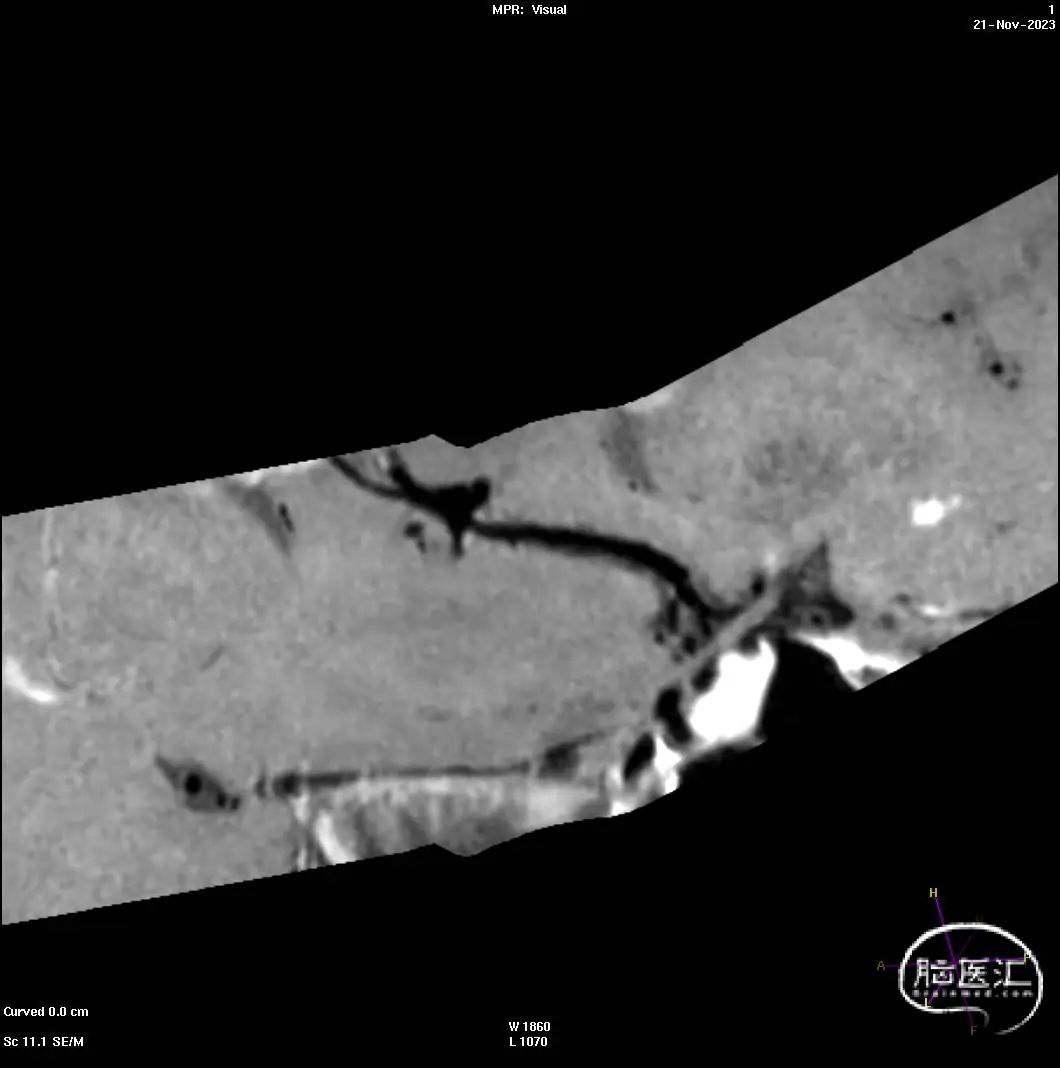

HRMR+CE-MRA:双侧大脑前动脉A2-A3段共干,并A3段远段不均匀梭形膨大,形态欠规则,膨大段管腔近端呈结节状,最大管径约4.4mm,增强扫描瘤壁未见确切强化,其近端共干动脉管径约2.2mm。

DSA 3D重建:

DSA 3D重建显示:

左侧大脑前动脉远侧段(A2-A5)动脉瘤,动脉瘤主体在A3段远端不均匀梭形膨大,形态欠规则,呈分页状态。

造影评估证实左侧大脑前动脉A3段梭形动脉瘤,标记测量动脉瘤最大直径5.8mm*3.91mm。近端血管直径2.77mm,远端血管直径2.62mm。

选择Evolve3.25*20支架顺利输送到位,采用推拉结合的方式释放支架。支架远端定位在A4段分叉以下,近端定位在A2段中部,完全覆盖病变部位。

术后即刻造影,动脉瘤体内出现明显造影剂滞留,远端各分支血管通畅,无造影剂滞留或外渗。

术后CT结果: